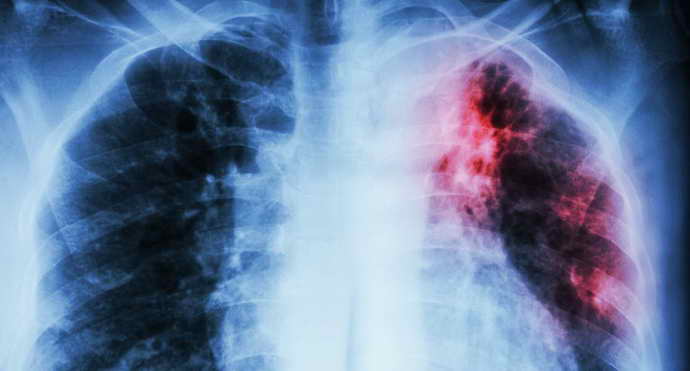

Туберкулез

Если диагностирован туберкулез воздухоносных путей, это негативно отражается на состоянии полости рта. Пациенты замечают на языке плотный налет белого цвета, который не убирается чисткой. Болезнь связана с тем, что в мягкие ткани мышечного органа проникли туберкулезные бактерии. На слизистой развиваются патологические бугорки, потом язвочки. Их размер постепенно растет. Изъязвления рыхлые, неглубокие, кровоточащие. Края их неровные. У таких больных повышается температура, появляется слабость, язвы резко болезненные. Отмечается повышенная потливость, исхудание. Кроме общей терапии рекомендовано местное лечение, назначается санация ротовой полости, когда наступает ремиссия. Патологические мягкие ткани обрабатываются антисептическими средствами.